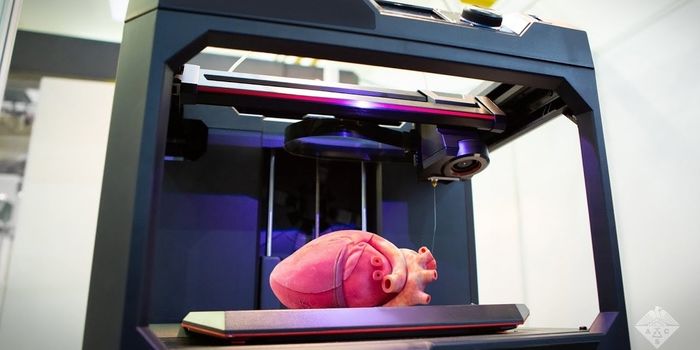

DEC 03, 2020Chemistry & PhysicsBuilding a realistic tissue model is critical for training young physicians and surgeons, and yet challenging due to the ...